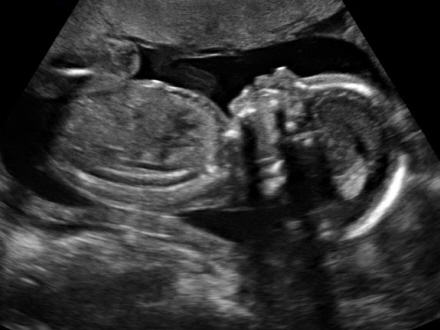

Medlem af Europa-Parlamentet Carlos Salvador mener, at kvinder, der overvejer abort, skal tvinges til at se billeder fra den første scanning af fosteret. Først derefter kan de få tilladelse til provokeret abort.

Skal se første scanning

Abortansøgeren skal nemlig modtage en forseglet kuvert med et billeder fra den første fosterscanning, oplysninger om støttenetværk og onformationer om, hvad en abort egentlig indebærer.

Salvador mener, at det vil få kvinderne til at tænke på fosteret som et levende væsen og ikke som en ”ting, der kan forsvinde ved et trylleslag”.